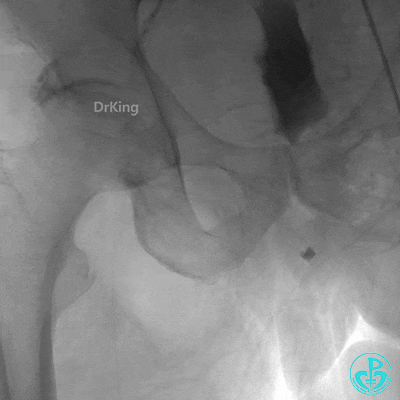

右冠脉支架通畅无狭窄,右冠脉给前降支远端提供逆向侧支循环。

EBU指引导管左冠脉造影显示粗大前降支中段闭塞,闭塞段近端有对角支发出,前降支同侧逆向显影,闭塞段不长。